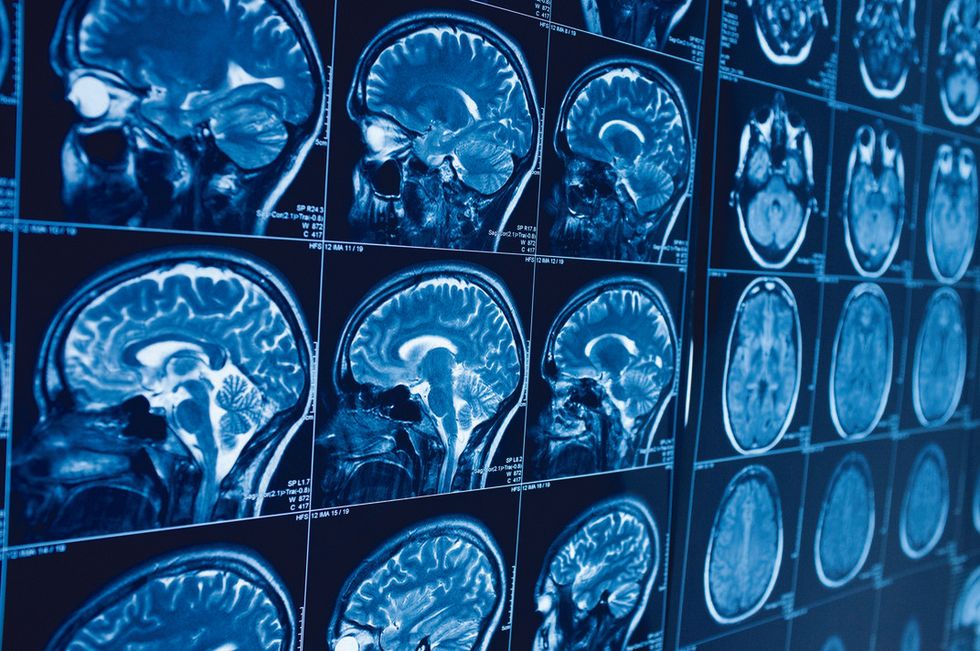

“Jani Ballta kishte vuajtur nga sëmundja idiopatike e Parkinsonit për më shumë se dymbëdhjetë vjet, duke përjetuar ngurtësi muskulore, vështirësi në ecje dhe dridhje të duarve. Pas aplikimit të një vlerësimi të plotë së bashku me ekspertët tanë të neurologjisë, të përbërë nga teste neurologjike dhe neuropsikologjike dhe një skanim MRI, ne përcaktuam se ai ishte një kandidat i mirë për operacionin e stimulimit të thellë të trurit dhe e kryem operacionin”, shpjegoi profesor Sabancı.